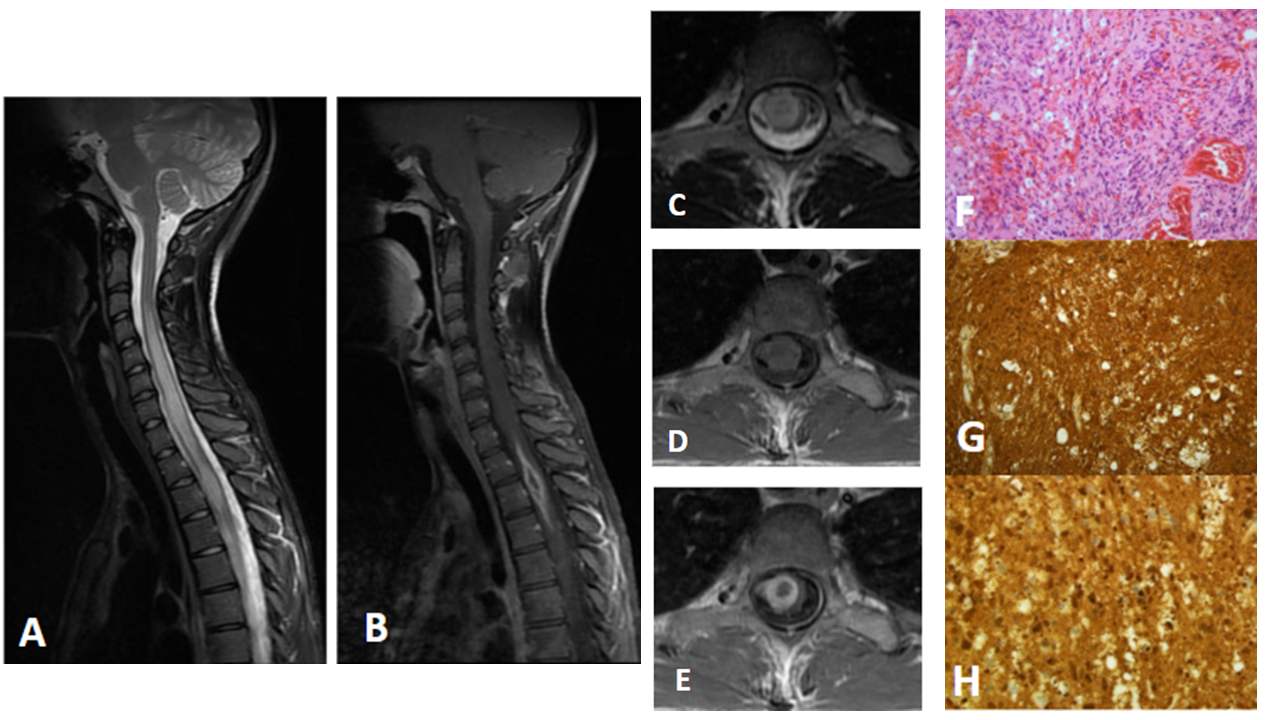

Figura A: RM de columna cervical potenciada en T2 en el plano sagital en la que se observa engrosamiento e hiperseñal T2 difusa del cordón medular desde C3-C4 hasta D6-D7.

Figura B: RM de columna cervical potenciada en T1 con gadolinio en el plano sagital en la que se observa lesión fusiforme con realce en anillo en los niveles D1-D3.

Figura C: RM de columna cervical potenciada en T2 en el plano axial en la que se observa lesión nodular intramedular a nivel de D3 que afecta principalmente la hemimédula derecha y asocia ensanchamiento del cordón medular. Es heterogénea con centro hipointenso y periferia hiperintensa.

Figura D: RM de columna cervical potenciada en T1 en el plano axial en la que se observa como la lesión es isointensa con la médula.

Figura E: RM de columna cervical potenciada en T1 con gadolinio en el plano axial en la que se observa un realce en anillo grueso tras la administración de contraste.

Figura F: Proliferación tumoral glial ricamente vascularizada y heterogénea constituida por células atípicas y pleomórficas con núcleos irregulares y algunos hipercromáticos, vesiculosos con cromatina gruesa dispersa y ocasionales nucléolos, con áreas de morfología epitelioide, fusocelulares, multinucleadas y otras de aspecto histiocitario, acompañada de algunos polimorfonucleares, cuerpos apoptóticos y restos nucleares con ocasionales mitosis. Se observa proliferación endotelial y focos de necrosis.

Figuras G y H: tumoración con técnicas de inmunohistoquímica positiva para PGFA y S100, respectivamente, siendo característico de tumores gliales.